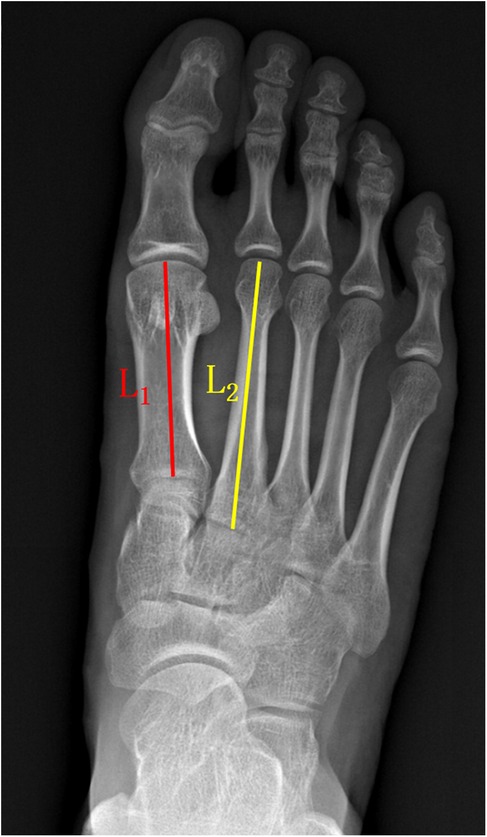

VAS (a numerical scale with a range from 0 to 10, where 0 represented “no pain” and 10 indicated “worst possible pain.”) and AOFAS-LMI scores were used to assess toe pain and function preoperatively and at 6 months postoperative, 1 year postoperative, and the final follow-up. The ROM of the metatarsophalangeal joint, including dorsiflexion and plantarflexion, was measured, and the total ROM was calculated. We measured active sagittal-plane range of motion (dorsiflexion and plantarflexion) of the second metatarsophalangeal (MTP) joint using a flexible, MTP-specific goniometer. With the patient supine or seated and the foot and ankle in neutral, the goniometer fulcrum was placed over the dorsal center of the second MTP joint. The proximal arm was aligned with the longitudinal axis of the second metatarsal, and the distal arm with the proximal phalanx. Patients were then instructed to actively move to end-range dorsiflexion and plantarflexion, at which point the angle was recorded (Figure 4). Metatarsal shortening was measured on weight-bearing anteroposterior x-rays of the foot using the following method. The preoperative length of the first metatarsal (L1 pre) and the second metatarsal (L2 pre) were measured using the first metatarsal length as a reference. At the final follow-up, the lengths of the first metatarsal (L1 post) and second metatarsal (L2 post) were measured, and the change in length (L0) was calculated as follows: L0 = L2 post/(L1 post/L1 pre) - L2 pre (Figure 5). Related complications (non-union, osteomyelitis, necrosis of the metatarsal head, or progression of metatarsophalangeal joint arthritis) were recorded.

X-ray of a foot showing bones with two marked lines for measurement. A red line labeled \\(L_1\\) runs along the first metatarsal, and a yellow line labeled \\(L_2\\) follows the second metatarsal.

Figure 5. The method used for measuring metatarsal bone length. The preoperative length was used as the reference standard. The length of the first metatarsal bone (L1 pre) and the second metatarsal bone (L2 pre) was measured before the surgery. At the final follow-up, the length of the first metatarsal bone (L1 post) and the second metatarsal bone (L2 post) was measured. The magnification factor for L2 post was calculated as L1 post/L1 pre, and the change in length for L2 (L0) was calculated as L0 = L2 post/(L1 post/L1 pre) - L2 pre.